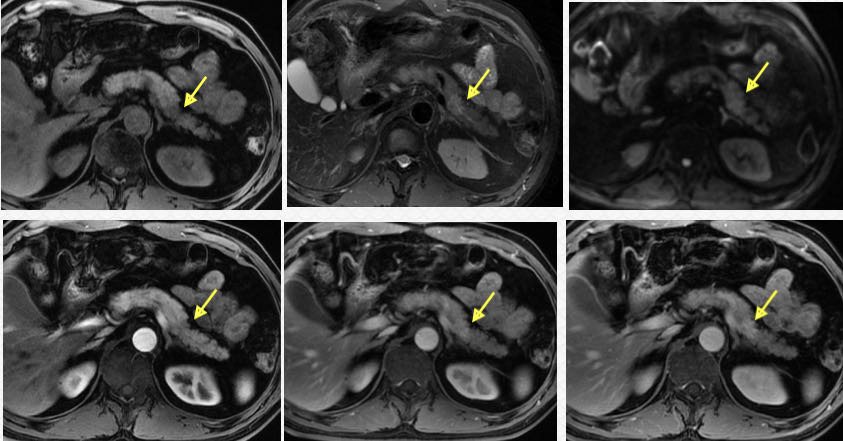

T1WI:实性占位

图5 实性浆液性囊腺瘤(SCN) T1WI显示病灶明显优于T2WI

(图片来源:余日胜教授讲课使用)

02

T2WI:囊性占位及纤维分隔

图6 胰腺囊性病灶及纤维分隔:T2WI